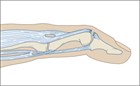

A patient arrives with a tender fingertip injury with a noticeable deformity. There is a history of a sudden resisted flexion of the distal interphalangeal (DIP) joint, such as when the fingertip is struck by a ball or jammed against a stationary object, resulting in pain and tenderness over the dorsum of the base of the distal phalanx. This injury can occur with relatively minor trauma (such as jamming a finger while reaching for a light switch in the dark) or even as a result of a direct blow to the dorsum of the finger. It may or may not be accompanied by swelling and ecchymosis over the DIP joint. When the finger is at rest or held in extension, the injured DIP joint remains in slight or moderate flexion (Fig. 106.1).